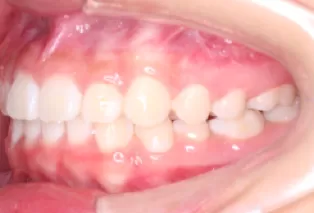

Intraoral photos